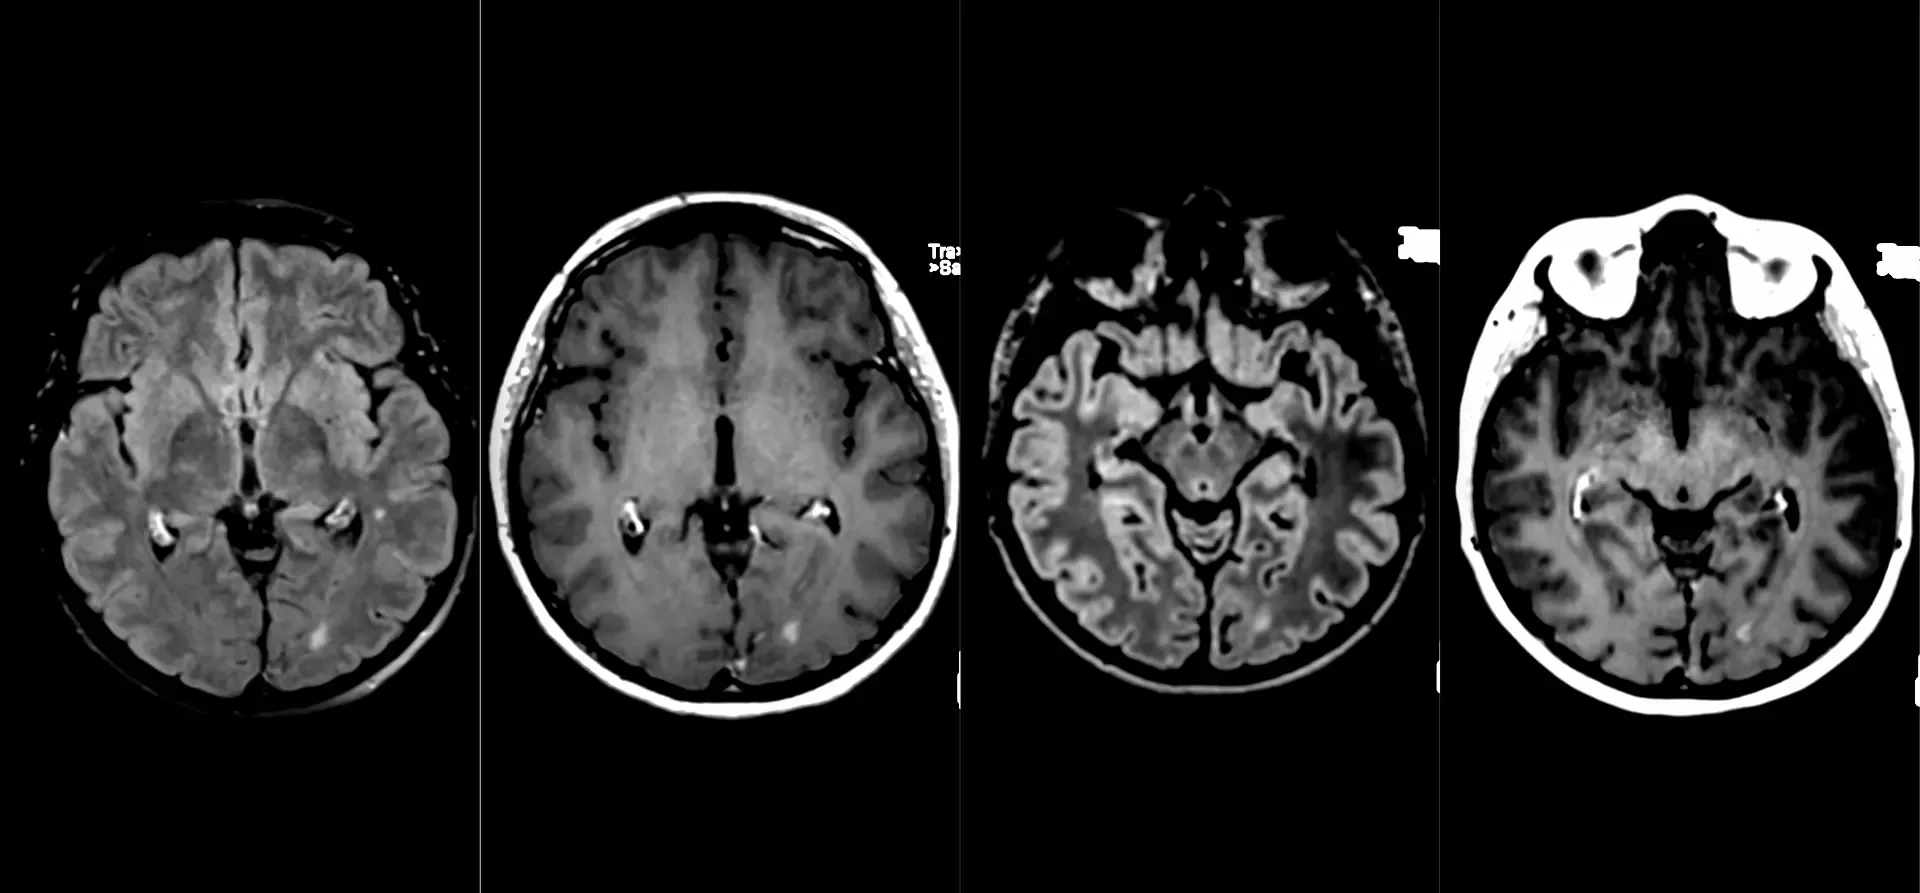

Клинический случай кавернозной мальформации, ассоциированной с венозной аномалией развития (ВАР). Следует напомнить, что ВАР часто сочетаются с каверномами, однако точные статистические данные не привожу, чтобы простимулировать самостоятельный поиск информации и закрепление знаний. Клиническая симптоматика у данного пациента отсутствует, что является типичным сценарием для подобных находок. Диагноз установлен случайно.